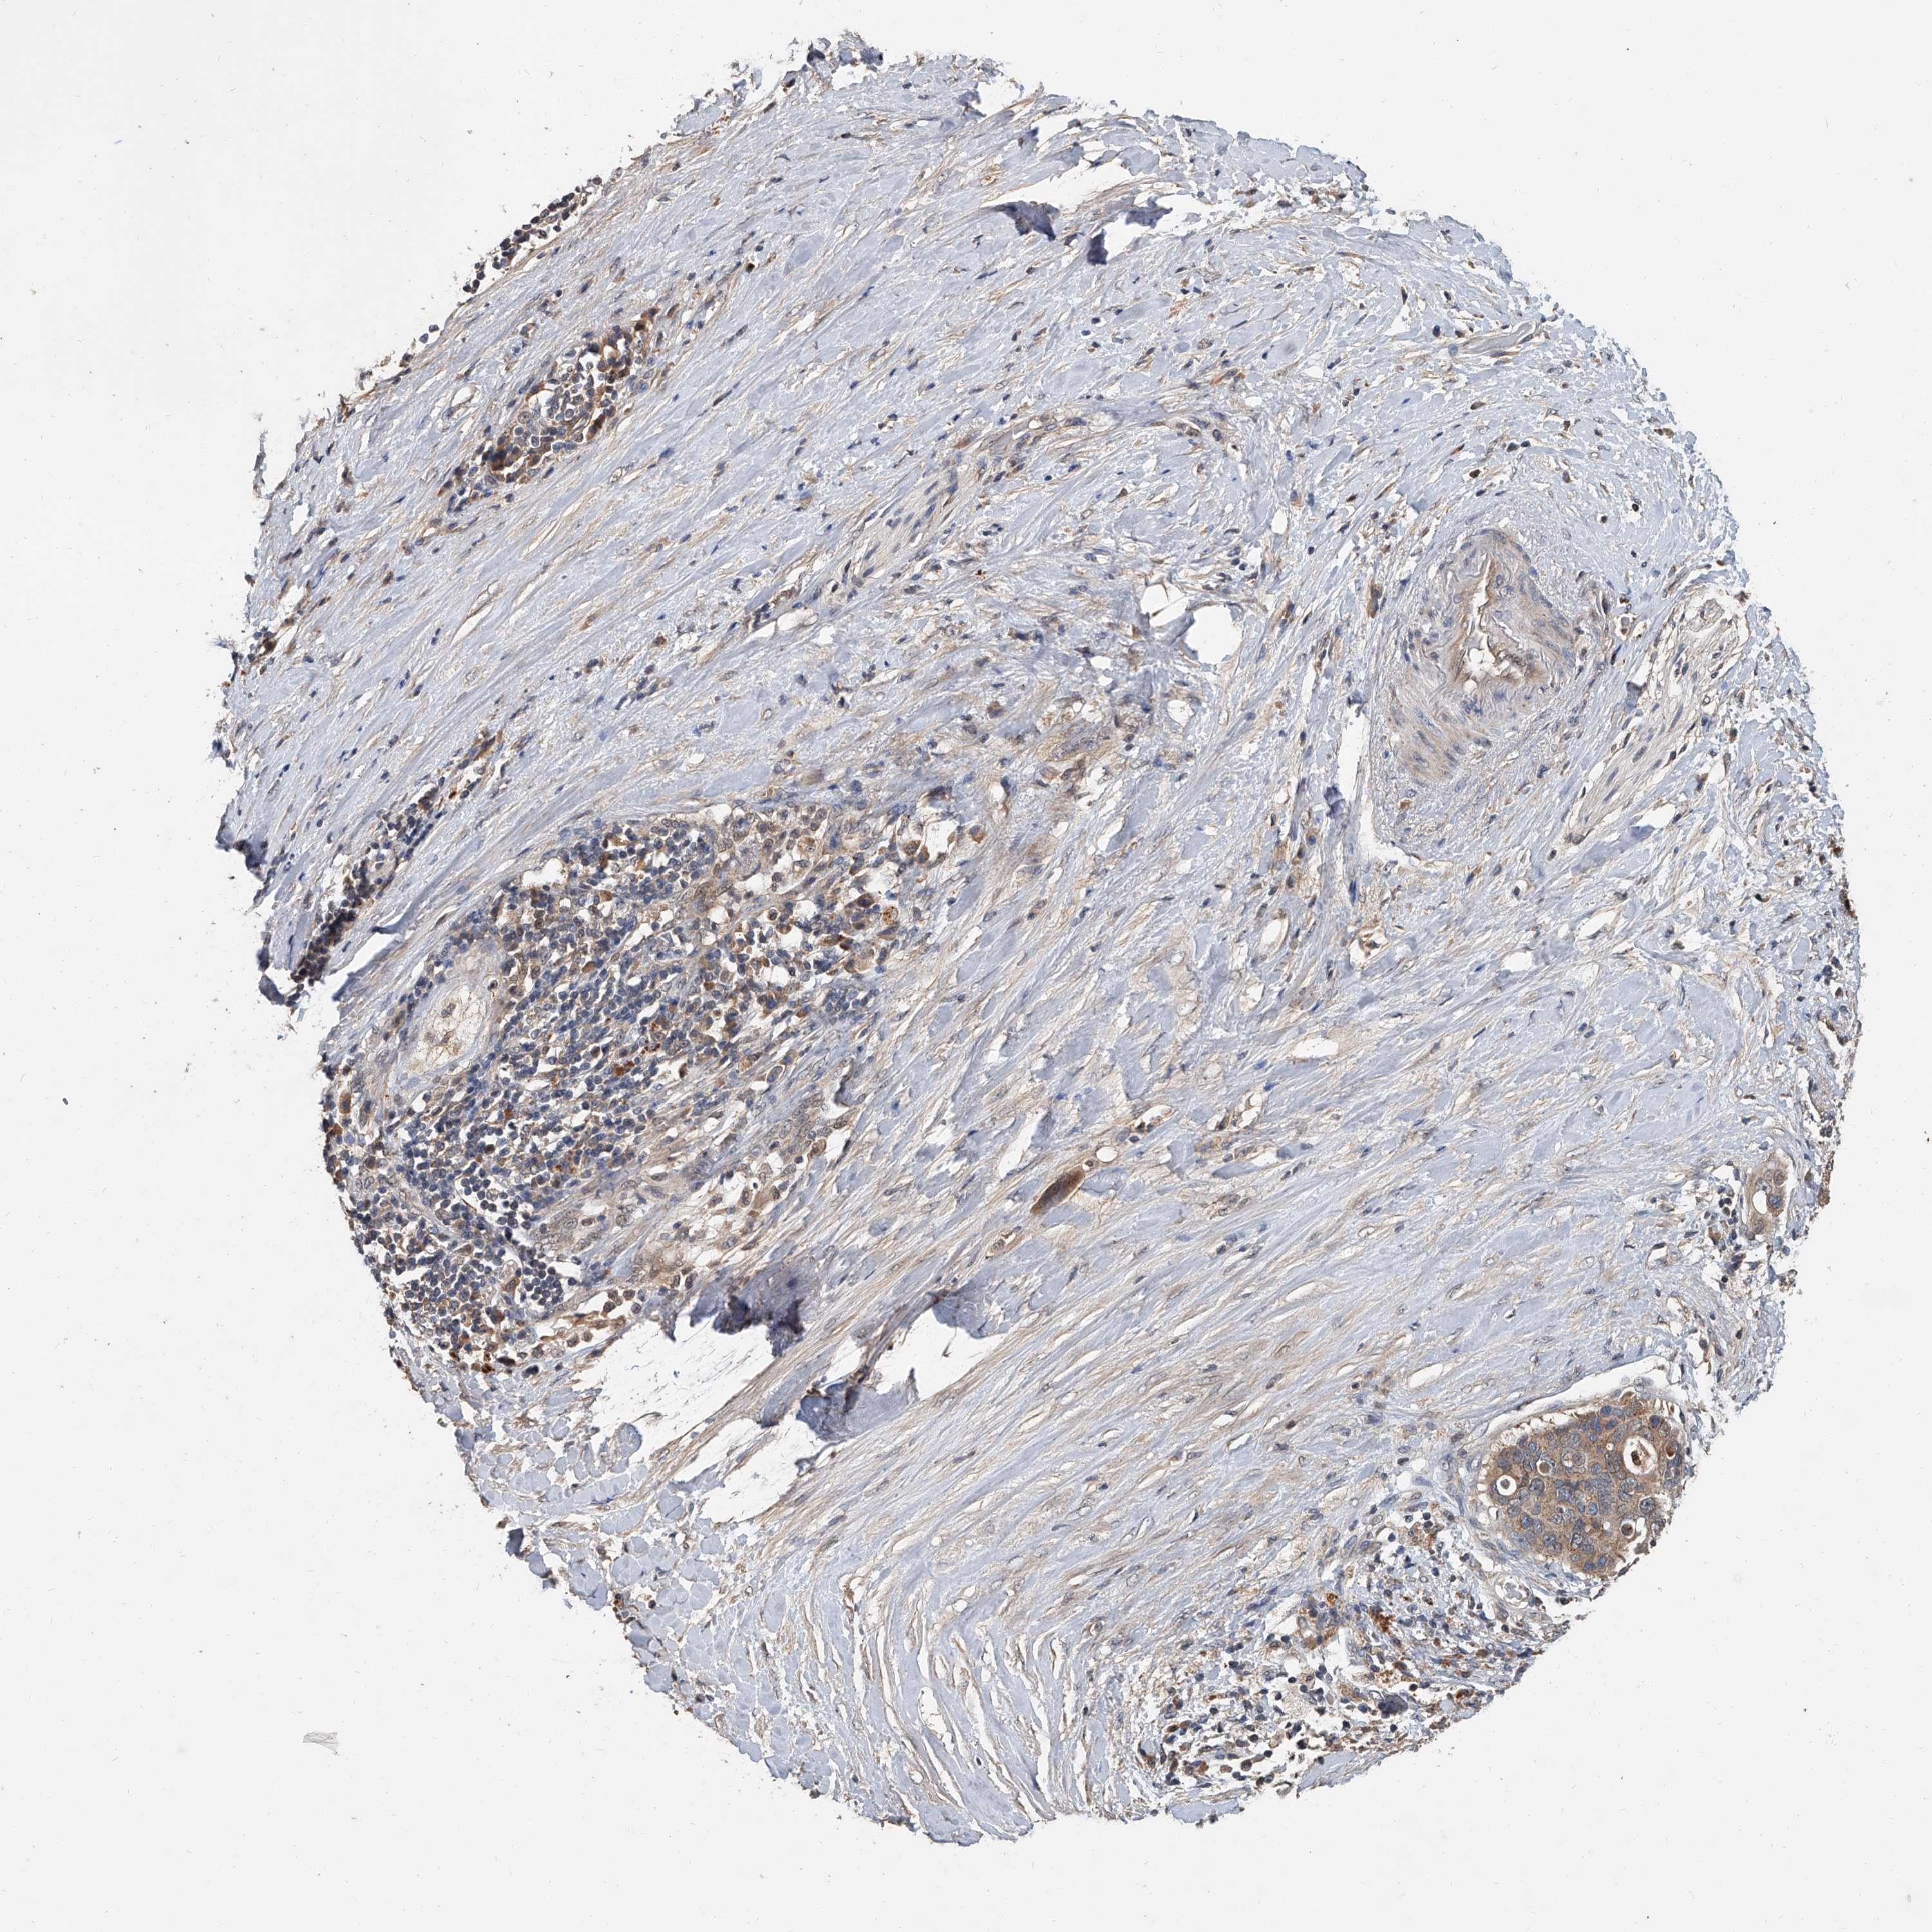

PANCREATIC CANCER - Protein expressioni

A mouse-over function shows sample information and annotation data. Click on an image to view it in a full screen mode. Samples can be filtered based on level of antibody staining by selecting one or several of the following categories: high, medium, low and not detected. The assay and annotation is described here.

Note that samples used for immunohistochemistry by the Human Protein Atlas do not correspond to samples in the TCGA dataset.

Antibody stainingi

Antibody staining in the annotated cell types in the current human tissue is reported as not detected, low, medium, or high, based on conventional immunohistochemistry profiling in selected tissues. This score is based on the combination of the staining intensity and fraction of stained cells.

Each image is clickable and will lead to virtual microscopy that enables deeper exploration of all samples and also displays staining intensity scores, fraction scores and subcellular localization as well as patient and tissue information for each sample.

Antibody HPA030636

Antibody CAB025481

Staining

High

Medium

Low

Not detected

Intensity

Strong

Moderate

Weak

Negative

Quantity

>75%

75%-25%

<25%

None

Location

Nuclear

Cytoplasmic/membranous

Cytoplasmic/membranous,nuclear

Adenocarcinoma, NOS